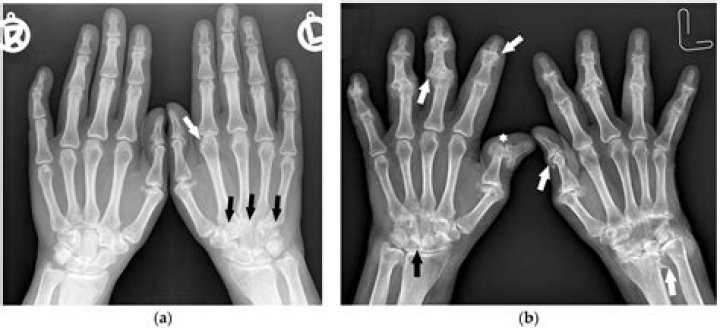

Hip osteoarthritis can be confirmed with x-rays. X-rays show: How much space there is between the femur and the acetabulum of the pelvic bone (the hip's ball and socket). No space or an abnormally small space indicates a loss of cartilage.

Medical imaging, including X-rays and magnetic resonance imaging (MRI), is crucial in diagnosing hip pain. An X-ray can reveal an excess of bone on the femoral head or neck and the acetabular rim. An MRI can reveal fraying or tears of the cartilage and labrum.

There is no single test for diagnosing osteoarthritis, but often it is diagnosed by an abnormal X-ray that shows characteristic features such as narrowing of the joint and spurring of the joint margins. Your doctor will take your medical history and perform a physical examination.